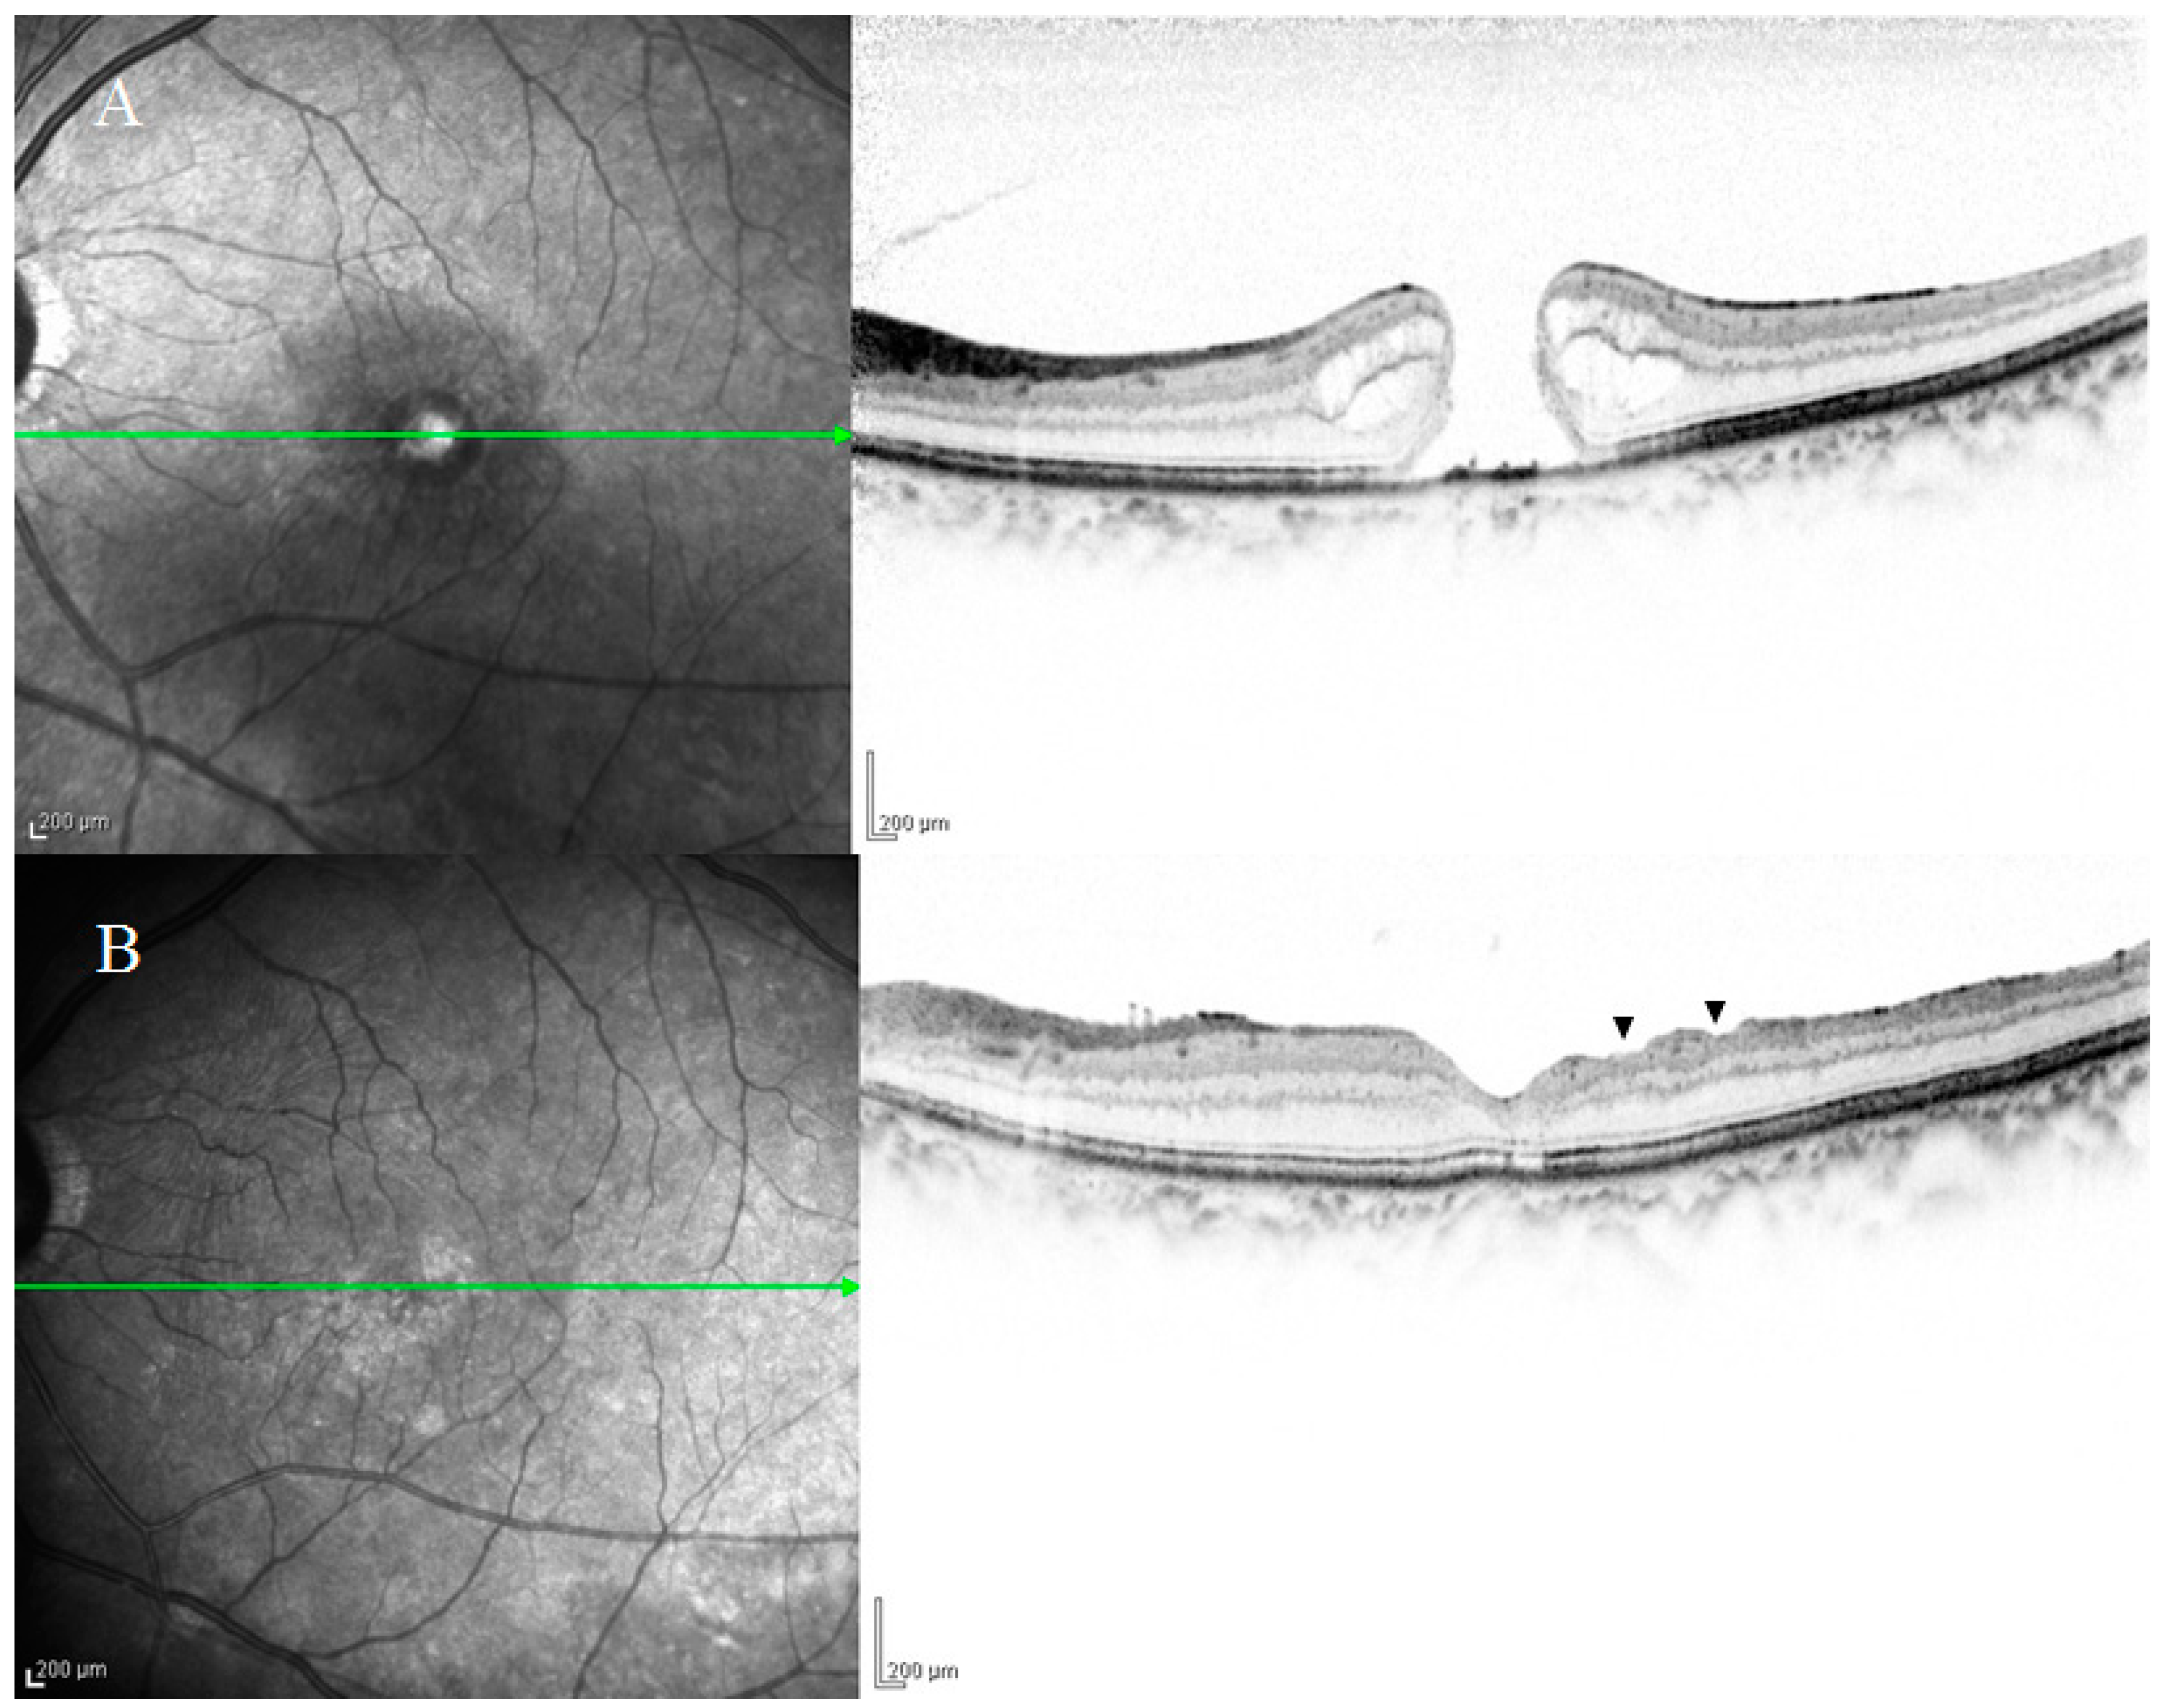

2. Anatomical Features of DONFL Appearance

2.1. DONFL Appearance and Visual Function

2.2. Previous Studies on the Pathogenesis of DONFL Appearance